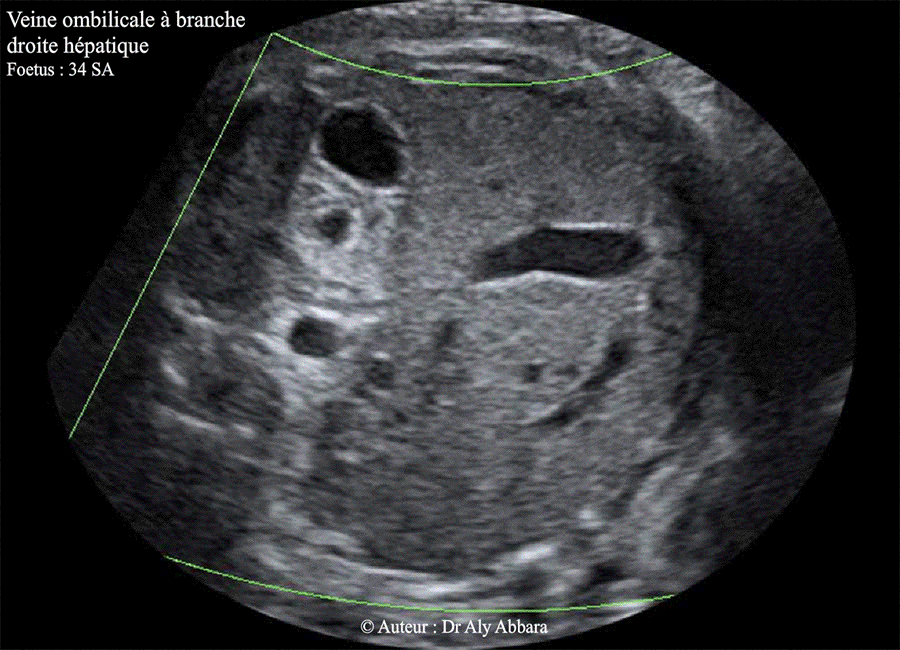

Images échographiques montrant une veine ombilicale gauche à branche droite intrahépatique.

(une variante de la persistance de la veine ombilicale droite ?).

Foetus de 34 SA ; aucune anomalie morphologique associée ; foetus eutrophe à la naissance.

a- Veine ombilicale gauche à branche droite intrahépatique

(le cas présenté dans cette page)